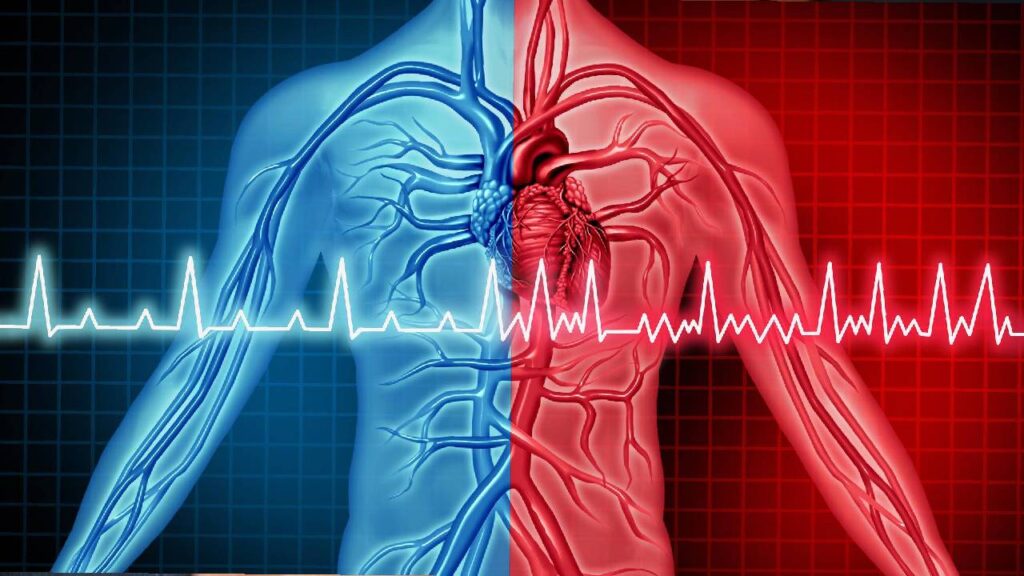

Heart health largely depends on daily food choices. At Pure Wellness, Clinical Nutritionist Dr. Priyanka Pawal provides professional Cardiac Diet Planning in Baner, Pune, focusing on improving heart health through balanced and therapeutic nutrition.

The cardiac diet plans are designed to help manage cholesterol levels, blood pressure, and overall cardiovascular health. Each plan is customized to support heart function, reduce risk factors, and promote long-term wellness.

• Improved heart health and circulation

• Better cholesterol and lipid control

• Reduced blood pressure levels

• Lower risk of heart attack and stroke